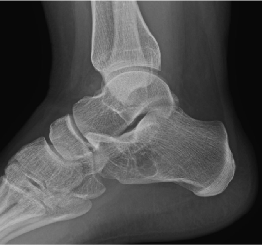

Bone cysts are rarely symptomatic but always problematic as they grow in size. Regardless of type, the potential for pathologic fracture is always present amongst our athletes and military. Evaluation and treatment are routinely an elective...